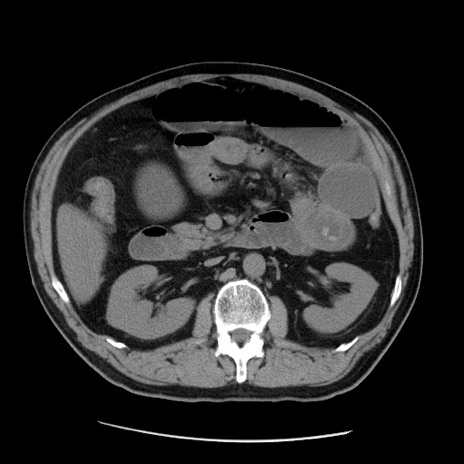

症例20(横断像)

【症例】 60歳代男性

【主訴】 腹部膨満、嘔吐

【現病歴】5日前頃より倦怠感を認め食事量減少し4日前の朝嘔吐、食事摂取困難となった。 3日前近医受診し点滴施行され整腸剤などを処方された。 当日他院を受診し、腹部膨満著明、炎症反応の上昇(CRP10.8、WBC11200)あり、紹介受診となる。

【身体所見】 意識JCS1 受け答えがはっきりしないBP 111/57mHg、 P 67bpm、、BT35.2°C、SpO2 97%(RA)、 腹部:膨隆、打診で鼓音あり、全体的に圧痛有り、腸蠕動音(-)、反跳痛ははっきりせず。

【データ】WBC 11400、CRP 14.20